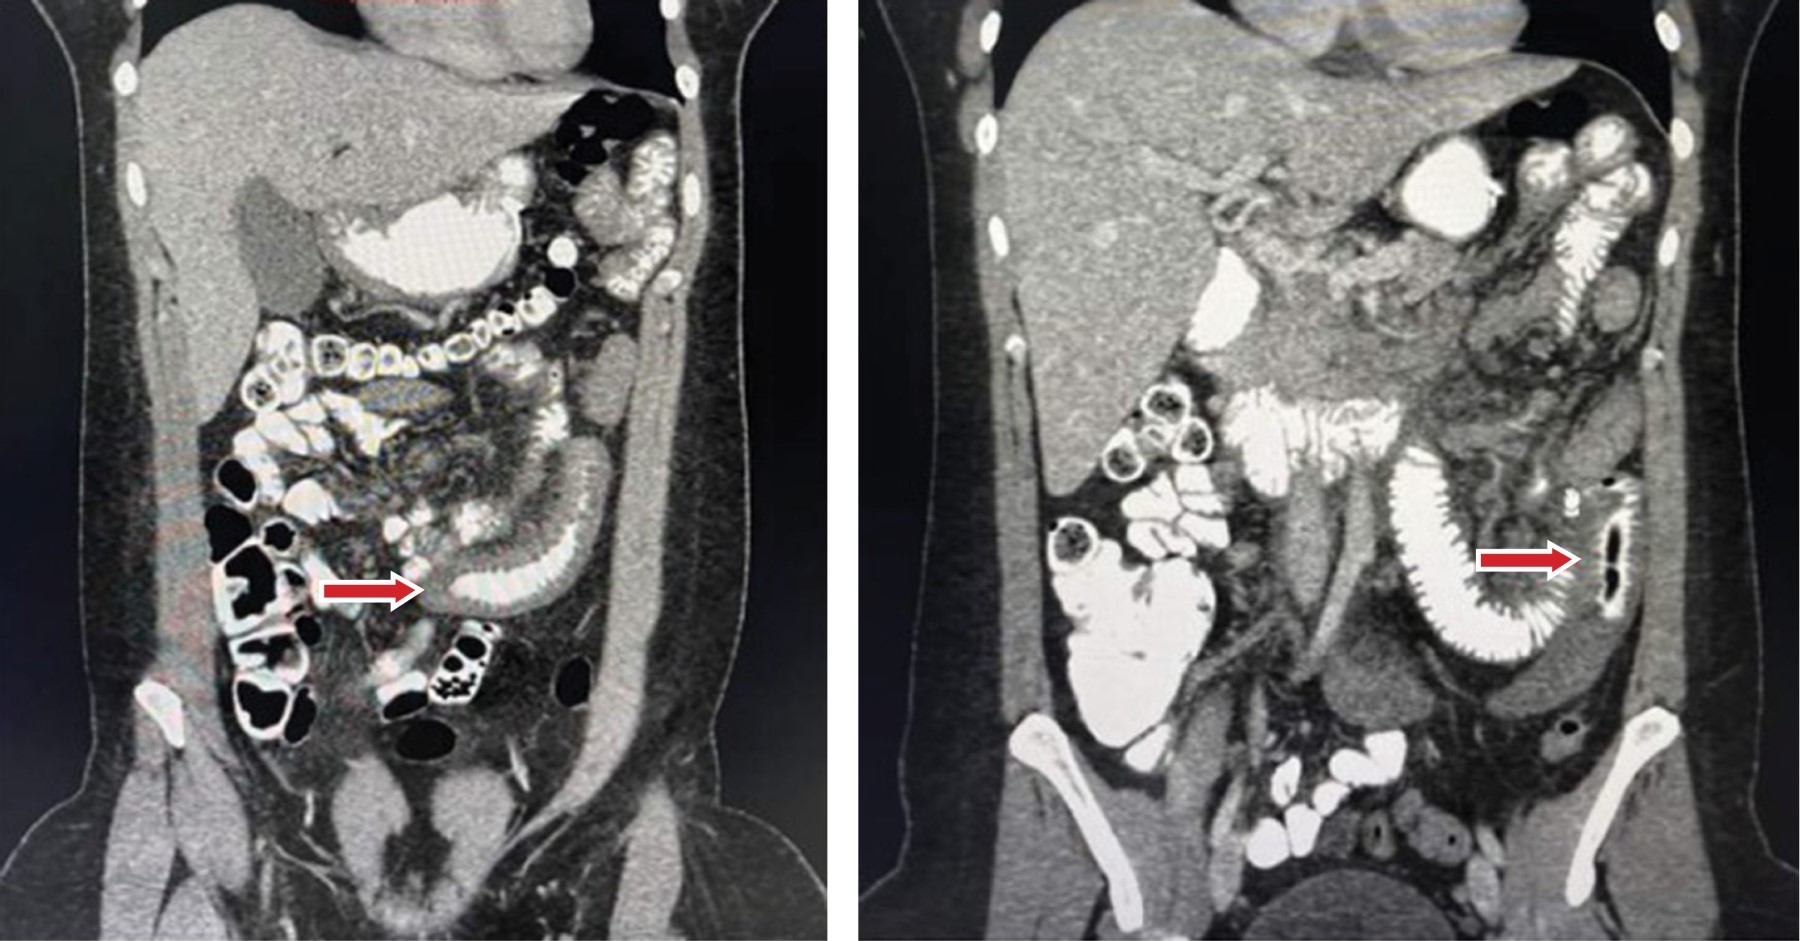

Introduction: An acute case of intestinal ischemia is a surgical emergency that could lead to abdominal sepsis, mesenteric or bowel infarction or even death. Amongst the new available measures to make an early diagnosis is the use of indocyanine green which has been used in hepato-biliary and oncologic surgery amongst others. However, there are only a few reports in the literature about its use in intestinal ischemia. Clinical case: This is the case of a 33-year-old female with abdominal pain and tomographic findings of an extense filling defect involving venous ileal branches, the superior mesenteric vein and partially the portal vein secondary to thrombosis and changes in the small bowel suggesting bowel ischemia. An exploratory laparoscopy was performed using indocyanine green to evaluate intestinal perfusion ruling out ischemia or necrosis. After further evaluation and with a multidisciplinary management to rule out prothrombotic states a second-look laparoscopy was performed using indocyanine green corroborating an adequate intestinal perfusion and intestinal viability. Her post-operative evolution was favorable and was discharged home. Conclusion: This case exemplifies how the use of indocyanine green has useful applications in the management of intestinal ischemia and can avoid unnecessary bowel resections.

Figure 2